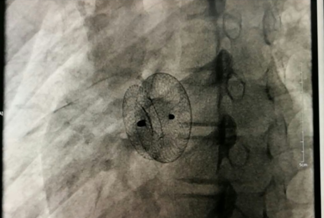

我院成功開(kāi)展市屬醫(yī)院首例先心病介入封堵術(shù)?不用開(kāi)刀,不會(huì)在體表留下疤痕,只需進(jìn)行局部皮膚麻醉,通過(guò)穿刺右側(cè)股靜脈插入一根幾毫米的導(dǎo)管,將封堵器送至缺損部位釋放,先天性心臟病就得到了根治。不久前,15歲的小章在我院成功接受了先天性心臟病介入封堵術(shù),他的心臟結(jié)構(gòu)和功能恢復(fù)了正常,學(xué)習(xí)和生活也得到了恢復(fù)。...